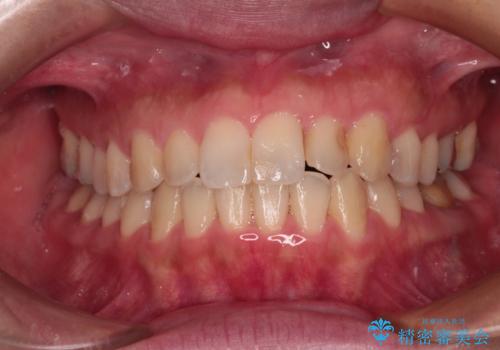

【モニター】上下前歯の叢生を解消 インビザライン矯正治療

- 前歯の捻れを気にして来院された患者様です。

上顎前歯が捻れて前方に飛び出しており、下顎前歯もそれに沿うようにデコボコとなっていました。

IPR(歯と歯の間を削る処置)によりスペースを獲得して上下前歯のデコボコを改善し、インビザラインにて矯正治療を行うこととしました。

捻れていた前歯の形態が、先端が欠けていたり、一部むし歯処置により左右非対称の形態となっていたため、なかなかゴールが定まらず、治療期間がかかってしまいました。